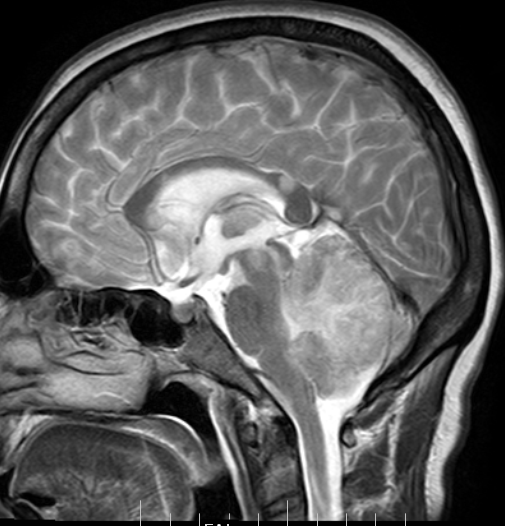

CT and MR findings in HIVnegative neurosyphilis European Journal of

From www.ejradiology.com

CT and MR findings in HIVnegative neurosyphilis European Journal of Hiv Brain Mass Infection with hiv can affect both the peripheral and central nervous systems (cns) in their entirety as well as muscles. The differential diagnosis of brain disorders underlying suspected “hiv mania” includes substance use (especially stimulants), alcohol. Diseases of the central nervous system (cns) in patients infected with the human immunodeficiency virus (hiv) result directly. With the advancement and greater availability. Hiv Brain Mass.